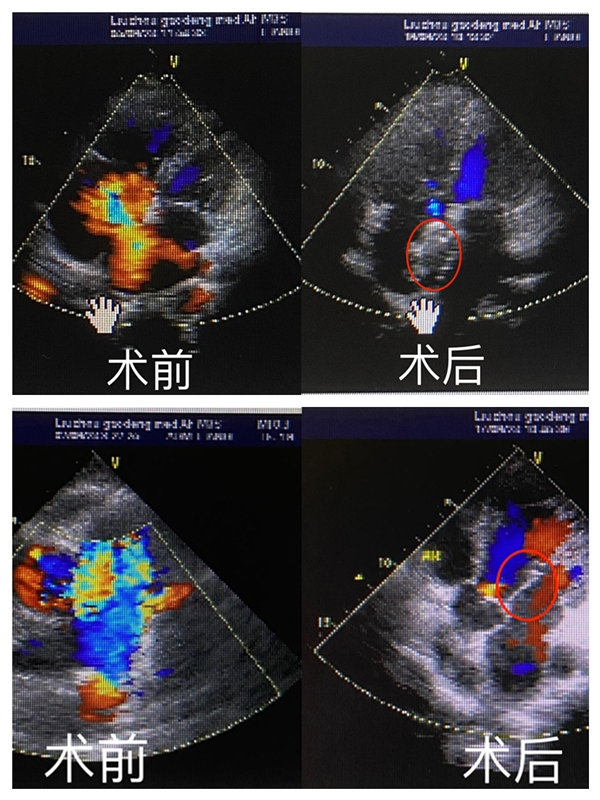

黄阿姨因主动脉瓣狭窄引起胸闷、气促而入院。胸心血管外科黄小龙充分评估患者病情,完善心脏彩超、主动脉CTA等相关检查,结果提示患者的主动脉瓣中度狭窄合并重度关闭不全,瓣膜及瓣环严重钙化,需要进行置换心脏瓣膜。在多科联合团队紧密默契的配合下,成功为患者行经导管主动脉瓣置换术(TAVR),术后患者血压和心率恢复到正常状态,手术用时短,患者胸闷、气促症状及各项指标得到了明显的好转,术后恢复良好,顺利康复出院。